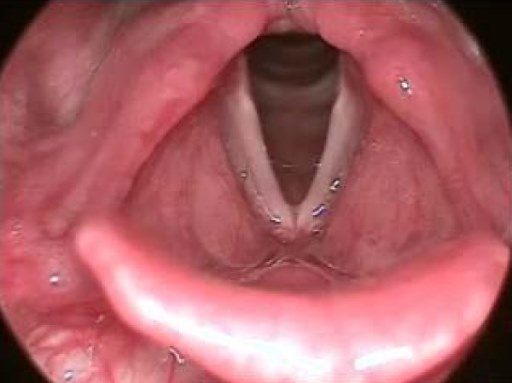

What is a laryngospasm?

- Closure of the vocal cords where the larynx closes the glottis by contracting.

- It is the body’s natural response to prevent substances from entering the lungs.

- If a complete obstruction occurs, the patient may experience hypoxia, no audible air entry, and bradycardia.